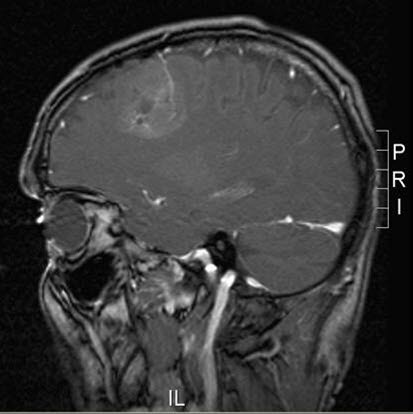

Oligodendrogliom, sagittalt snitt

Gjengitt med tillatelse av Radiologisk avdeling, Universitetssykehuset Nord-Norge